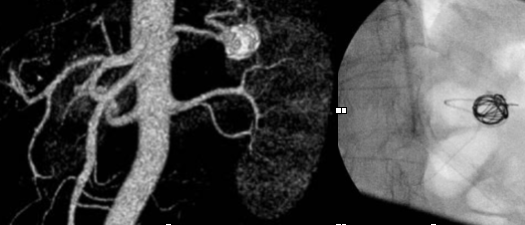

Aneurismas esplénicos, cuáles son sus riesgos y cómo tratarlos

La arteria esplénica es una de las tres ramas que forman el tronco celíaco que tiene su origen en la aorta abdominal. Esta arteria proporciona flujo sanguíneo al bazo. Los […]